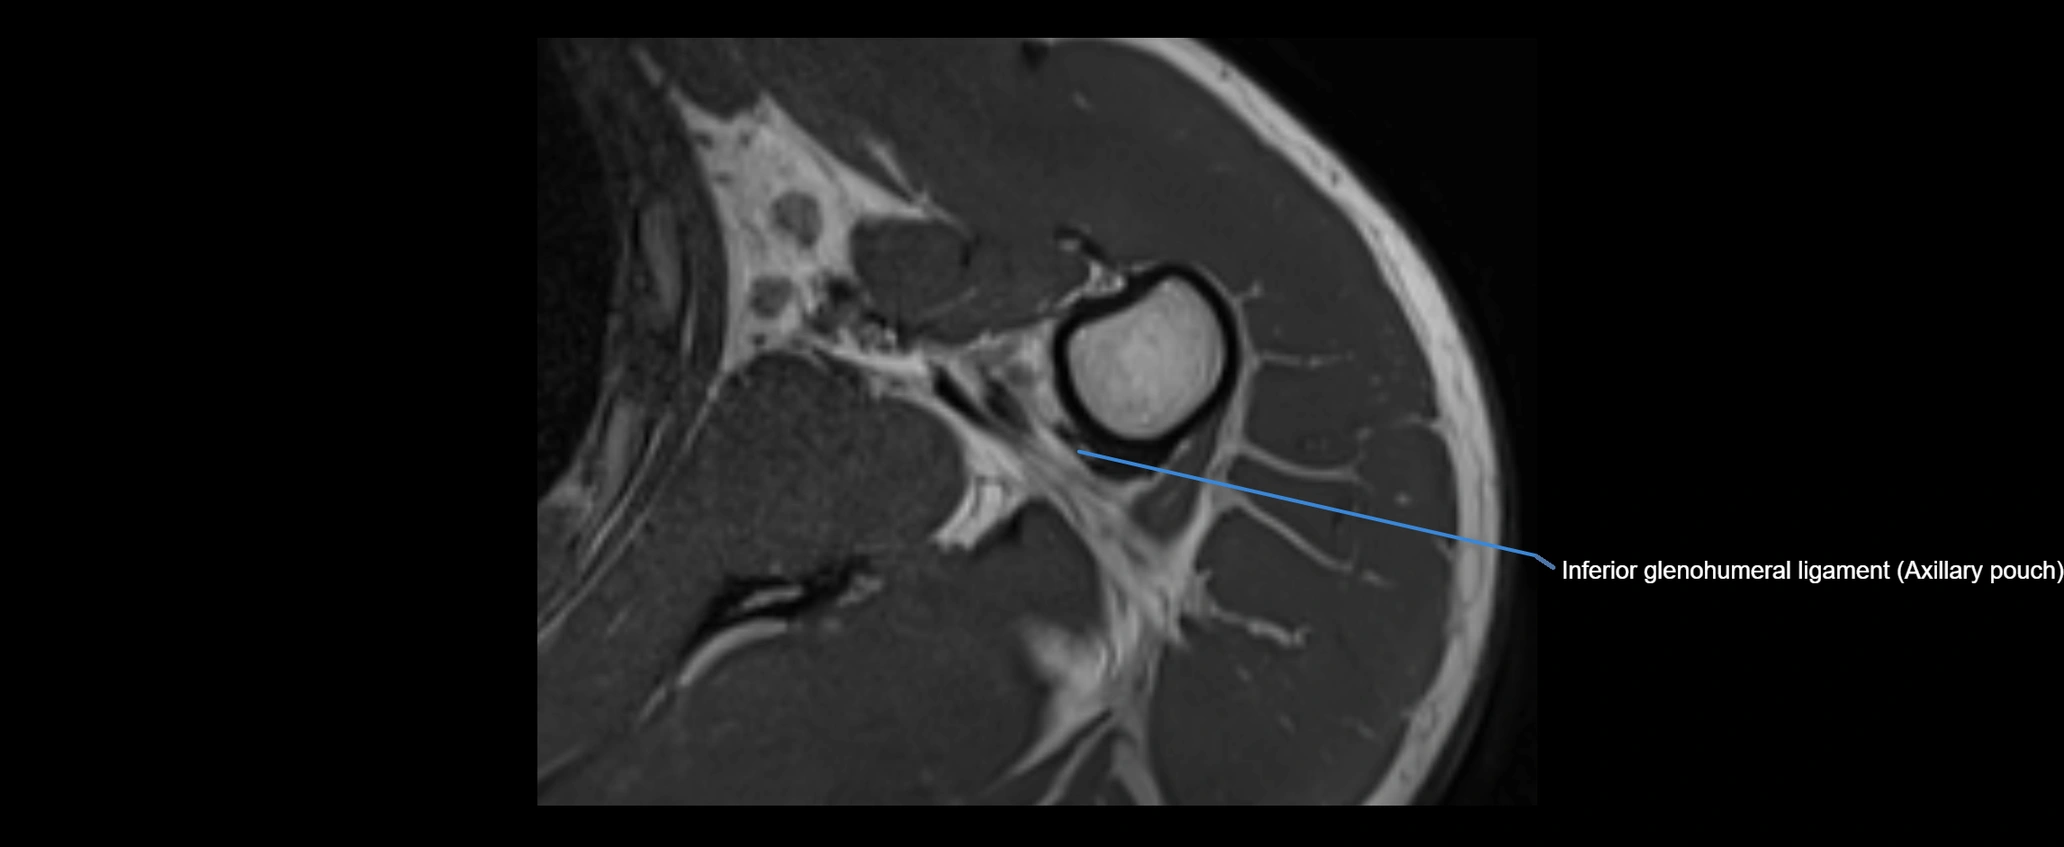

MRI images

image